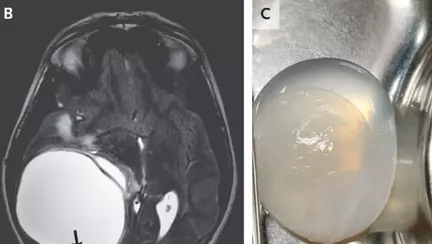

Un adolescent, în vârstă de 14 ani, a fost operat pentru a i se înlătura o tumoare uriașă de pe creier, apărută după ce s-a infectat cu viermi paraziți. Adolescentul, fără probleme medicale, locuiește într-o fermă din India. El a ajuns la medic după ce, timp de o lună, a acuzat dureri mari de cap